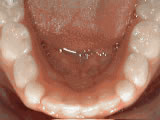

Spacing of teeth

spacing of teeth beforeBefore

spacing of teeth afterAfter

Patient was bothered by the spaces between his teeth. Braces closed the spaces and gave him an ideal bite in 24 months. Special glued-in retainers help keep the spaces closed.